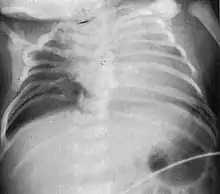

Characteristic radiograph from child with Jarcho-Levin syndrome, spondylocostal dysostosis subtype

In contrast to STD, the subtype spondylocostal dysostosis, or SCD features intrinsic rib anomalies, in addition to vertebral anomalies. Intrinsic rib anomalies include defects such as bifurcation, broadening and fusion that are not directly related to the vertebral anomalies (such as in STD, where extensive posterior rib fusion occurs due to segmentation defects and extreme shortening of the thoracic vertebral column).[6] In both subtypes, the pulmonary restriction may result in pulmonary hypertension, and have other potential cardiac implications.[7]